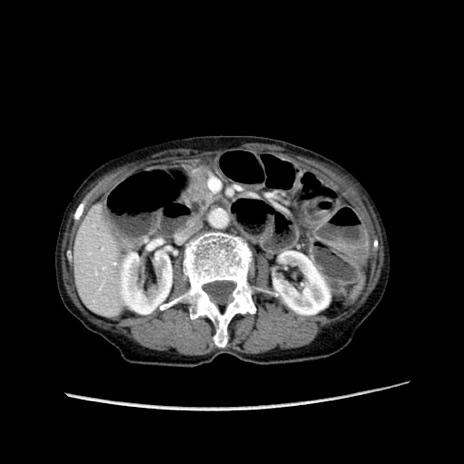

症例

冠状断像